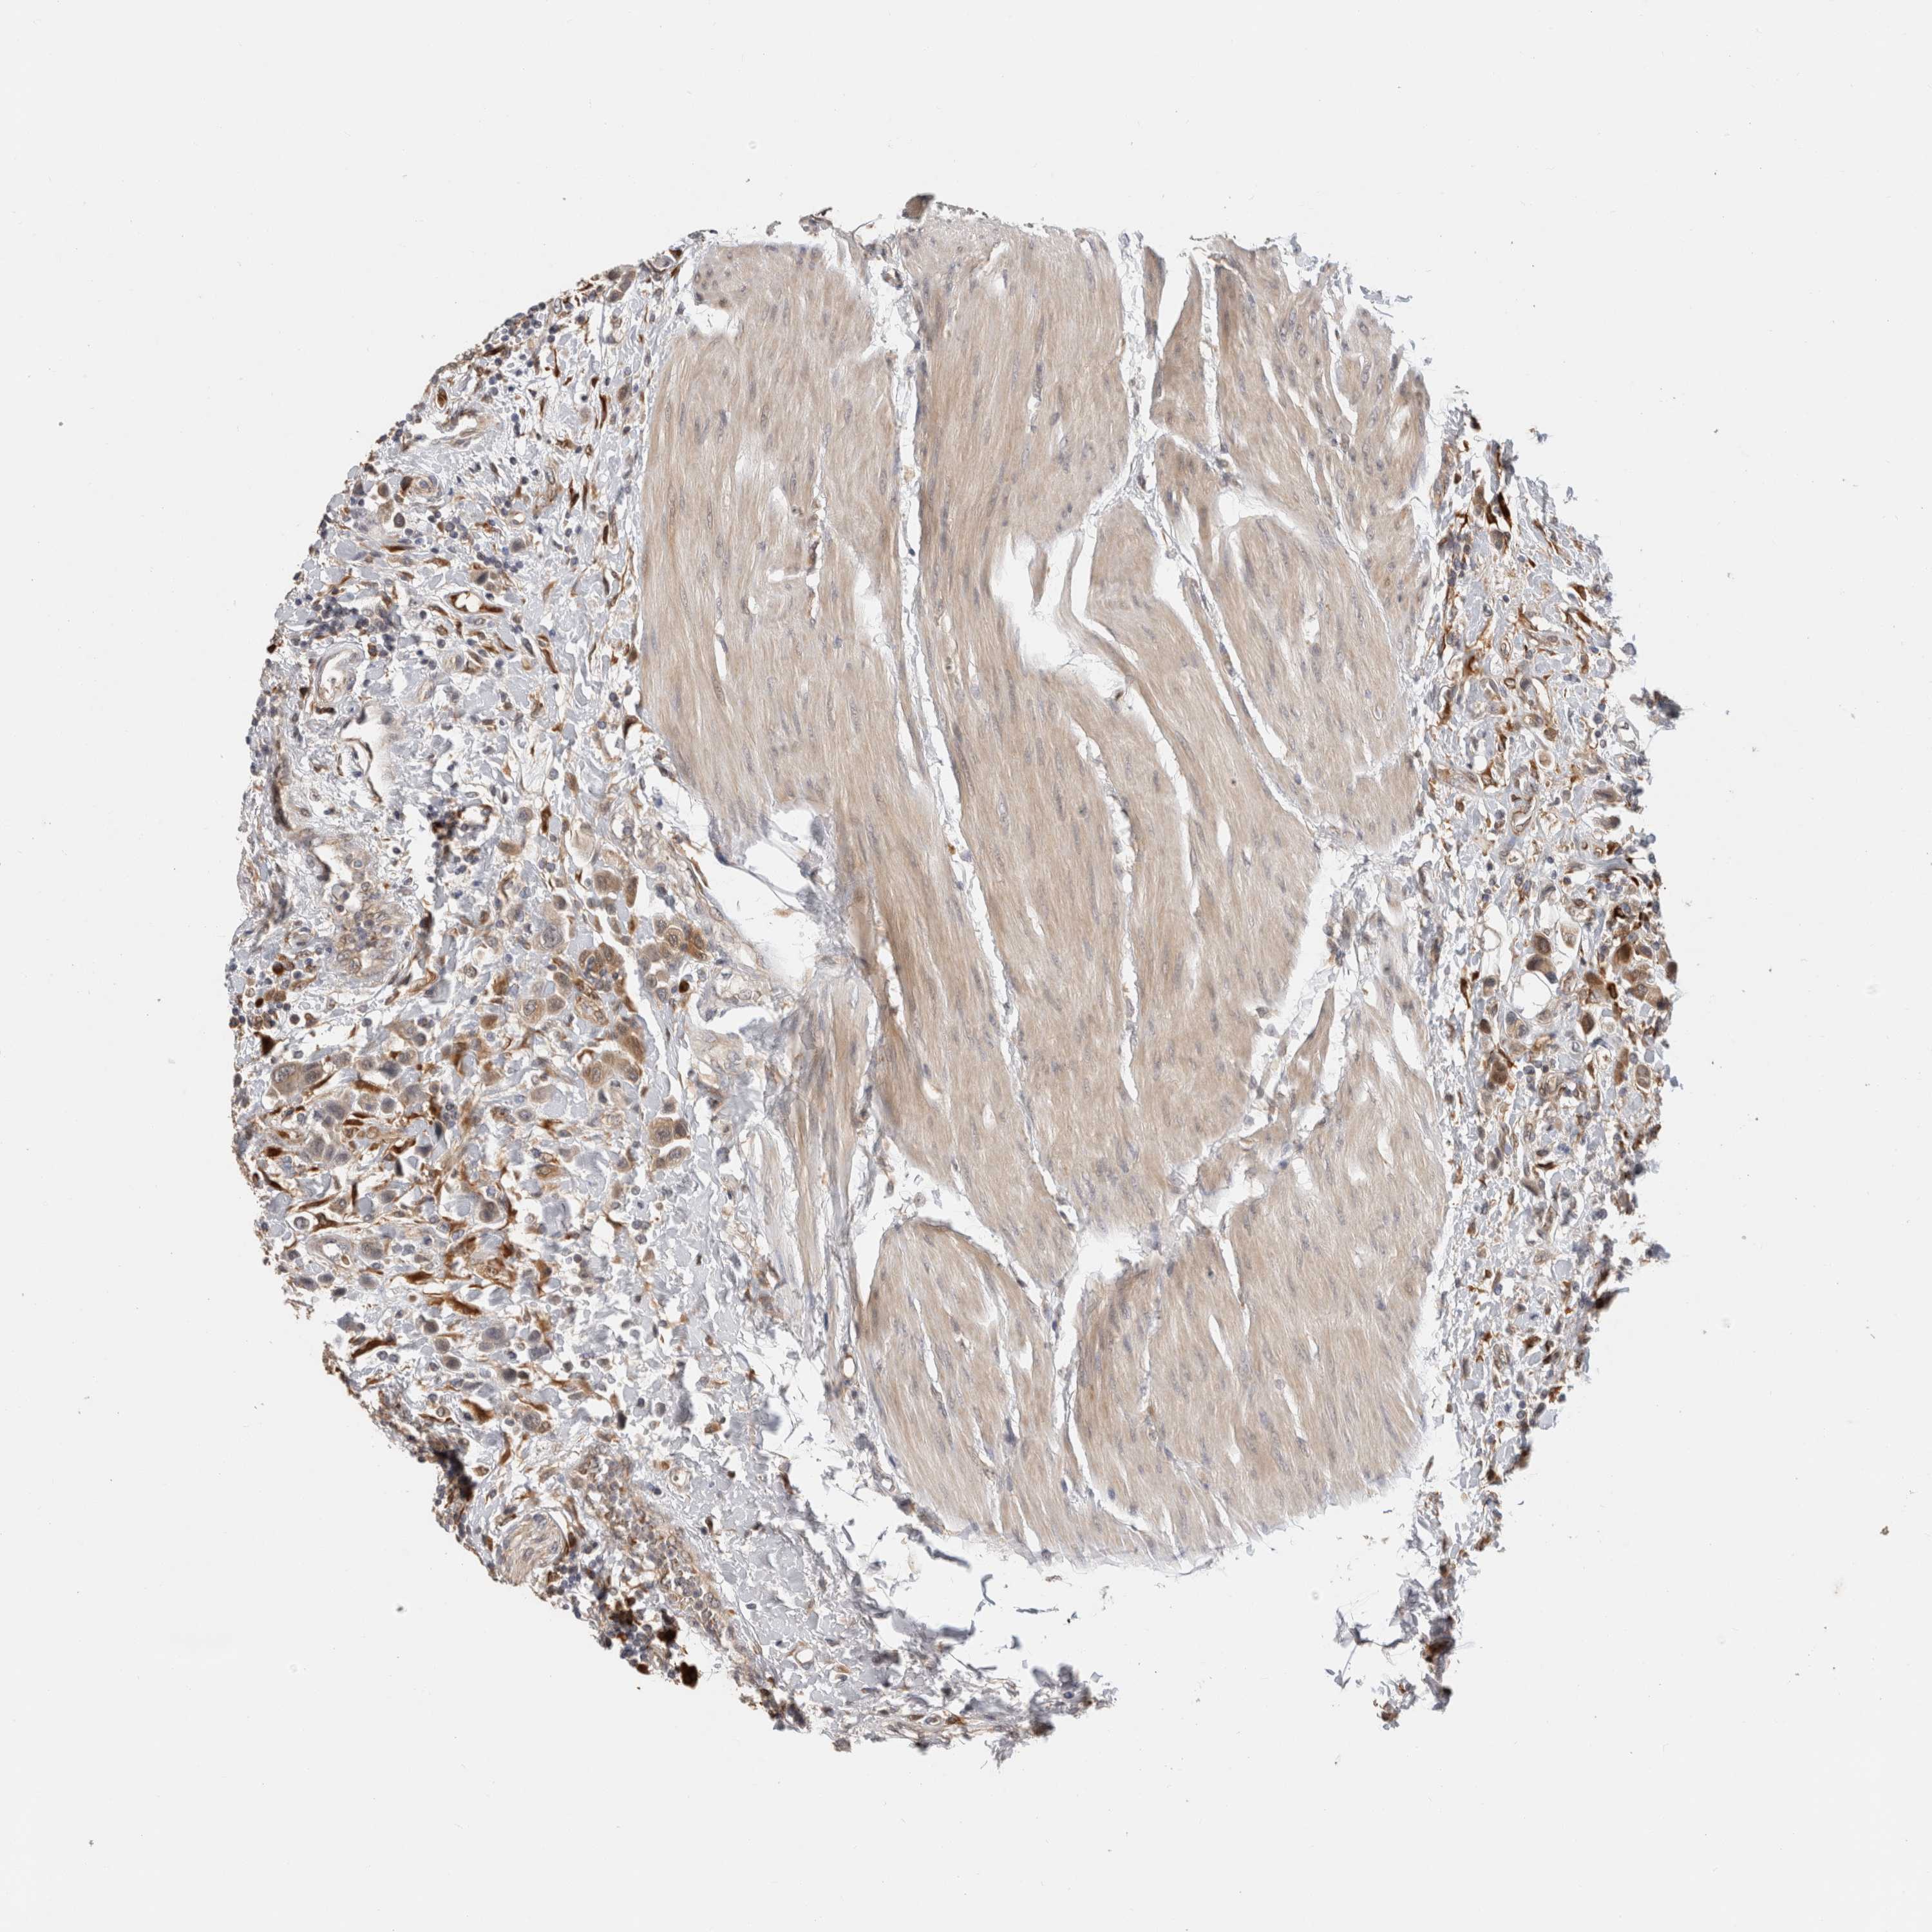

UROTHELIAL CANCER - Protein expressioni

A mouse-over function shows sample information and annotation data. Click on an image to view it in a full screen mode. Samples can be filtered based on level of antibody staining by selecting one or several of the following categories: high, medium, low and not detected. The assay and annotation is described here.

Note that samples used for immunohistochemistry by the Human Protein Atlas do not correspond to samples in the TCGA dataset.

Antibody stainingi

Antibody staining in the annotated cell types in the current human tissue is reported as not detected, low, medium, or high, based on conventional immunohistochemistry profiling in selected tissues. This score is based on the combination of the staining intensity and fraction of stained cells.

Each image is clickable and will lead to virtual microscopy that enables deeper exploration of all samples and also displays staining intensity scores, fraction scores and subcellular localization as well as patient and tissue information for each sample.

Antibody HPA001078

Antibody CAB026695

Staining

High

Medium

Low

Not detected

Intensity

Strong

Moderate

Weak

Negative

Quantity

>75%

75%-25%

<25%

None

Location

Nuclear

Cytoplasmic/membranous

Cytoplasmic/membranous,nuclear

Urothelial carcinoma, High grade

Urothelial carcinoma, Low grade

Adenocarcinoma, NOS